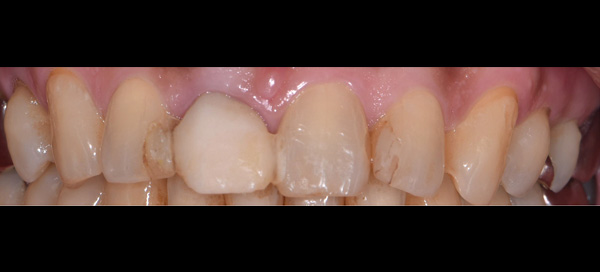

| 主訴 | 前歯が腫れた |

| 治療期間 | 約18ヶ月 |

| 費用 | 700,000円 |

| 治療内容 | インプラント、部分矯正、骨造成、結合組織移植、セラミック修復 |

| 治療に伴うリスク | インプラント周囲炎 セラミックの破折、脱離 |